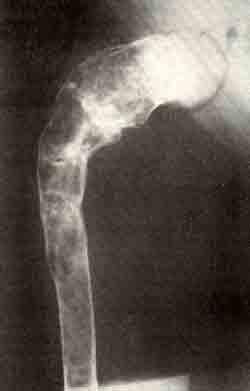

Деформация бедер по типу пастушьей палки

Деформация бедер по типу пастушьей палки, выраженная атрофия мышц и укорочение ноги при фиброзной остеодисплазии: фотография больного, видны деформация бедер с пигментными пятнами и рентгенограмма бедра е типичной деформацией.

На сегментах с большим поражением кости резко бросается в глаза выраженная мышечная атрофия. Эпифизарный рост нарушается редко. Для отдельных костей при фиброзной дисплазии существуют характерные деформации. Большеберцовая кость искривляется в средней трети выпуклостью вперед, бедро — в верхней трети по типу пастушьей палки.